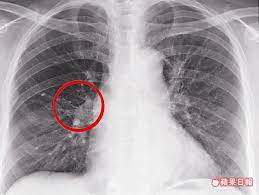

背痛月餘竟是肺腺癌啃掉肋骨 蘋果日報 medical news abstract artwork abstract